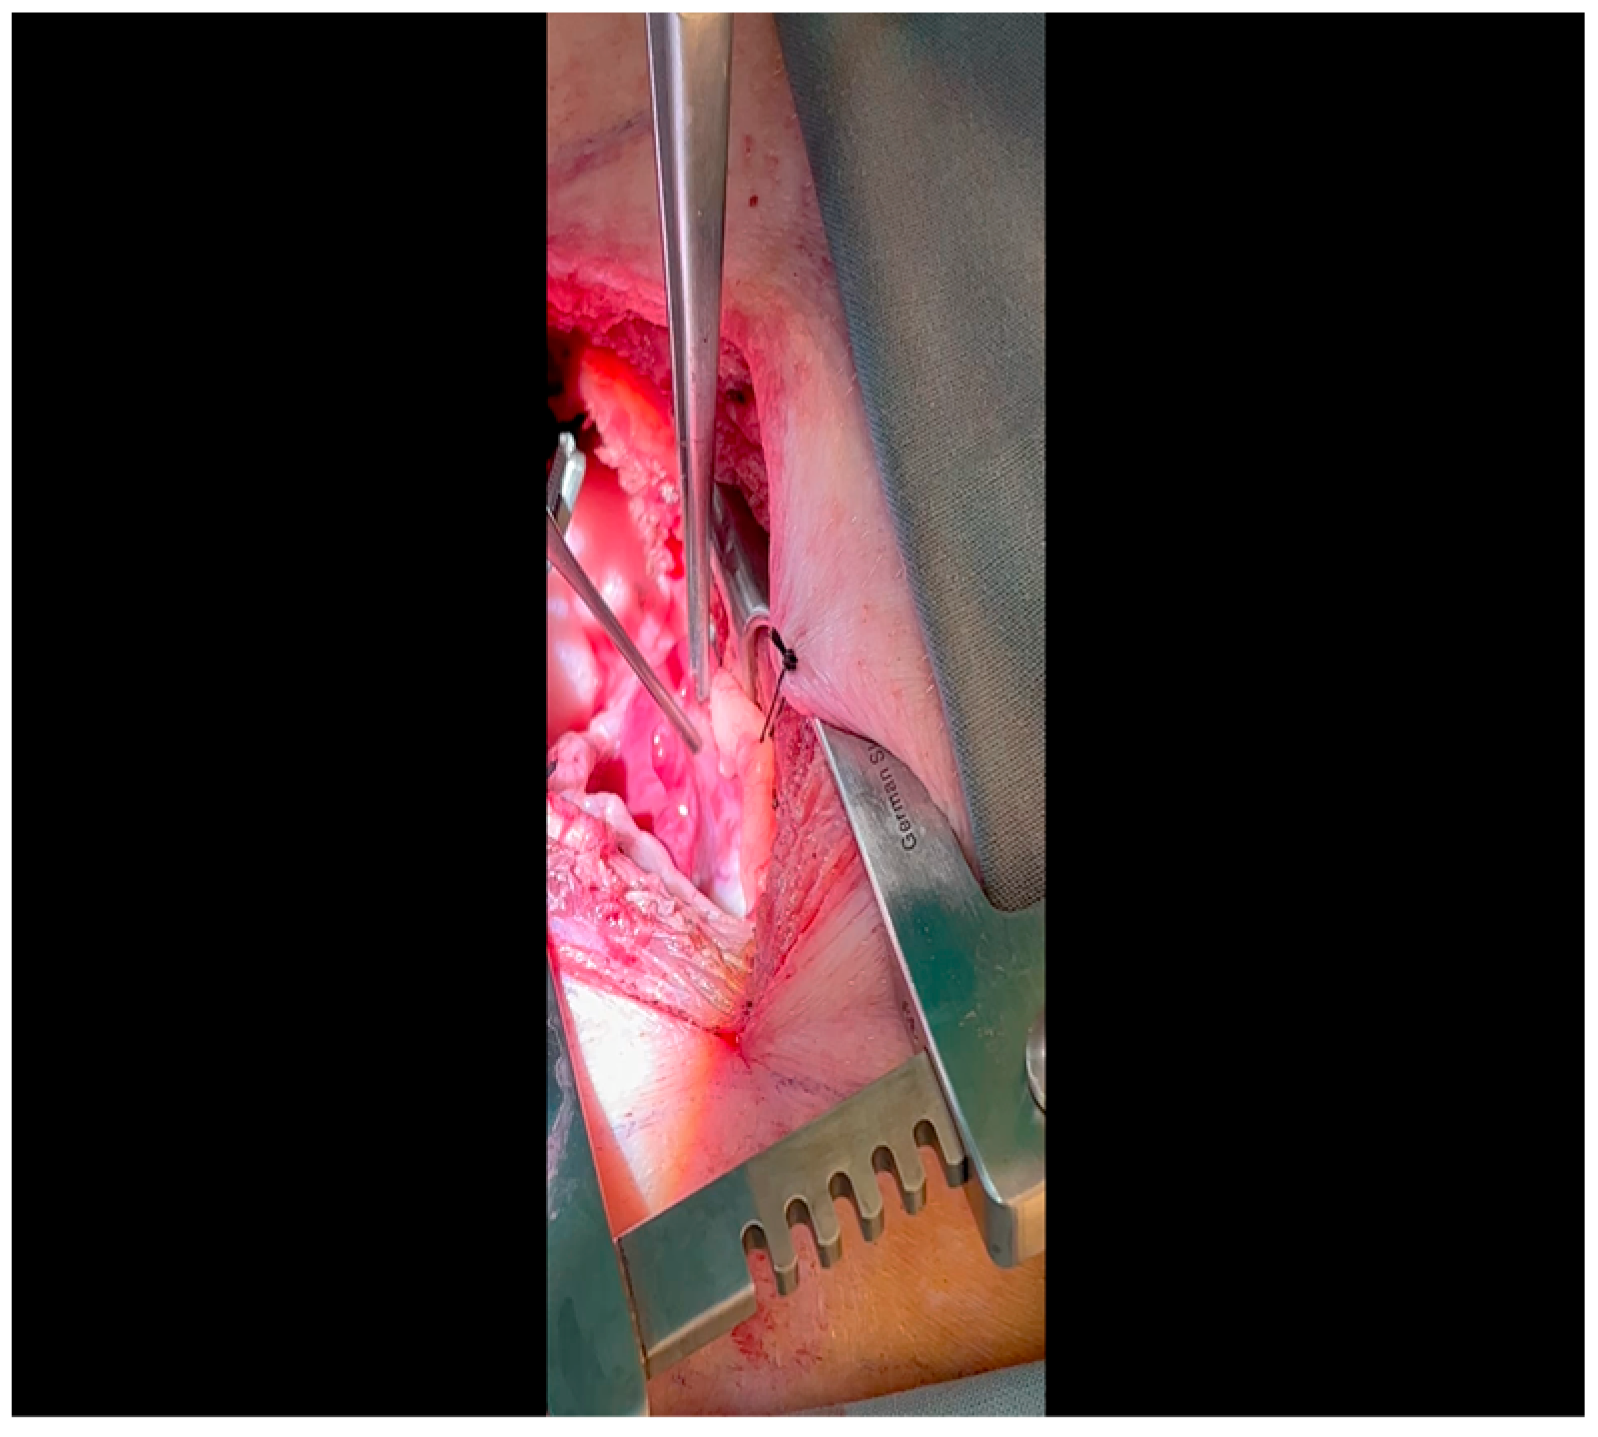

- A 3-0 silk suture secures the pericardium to the skin, elevating the heart into the surgical field and retracting the pericardium (Figure 4).